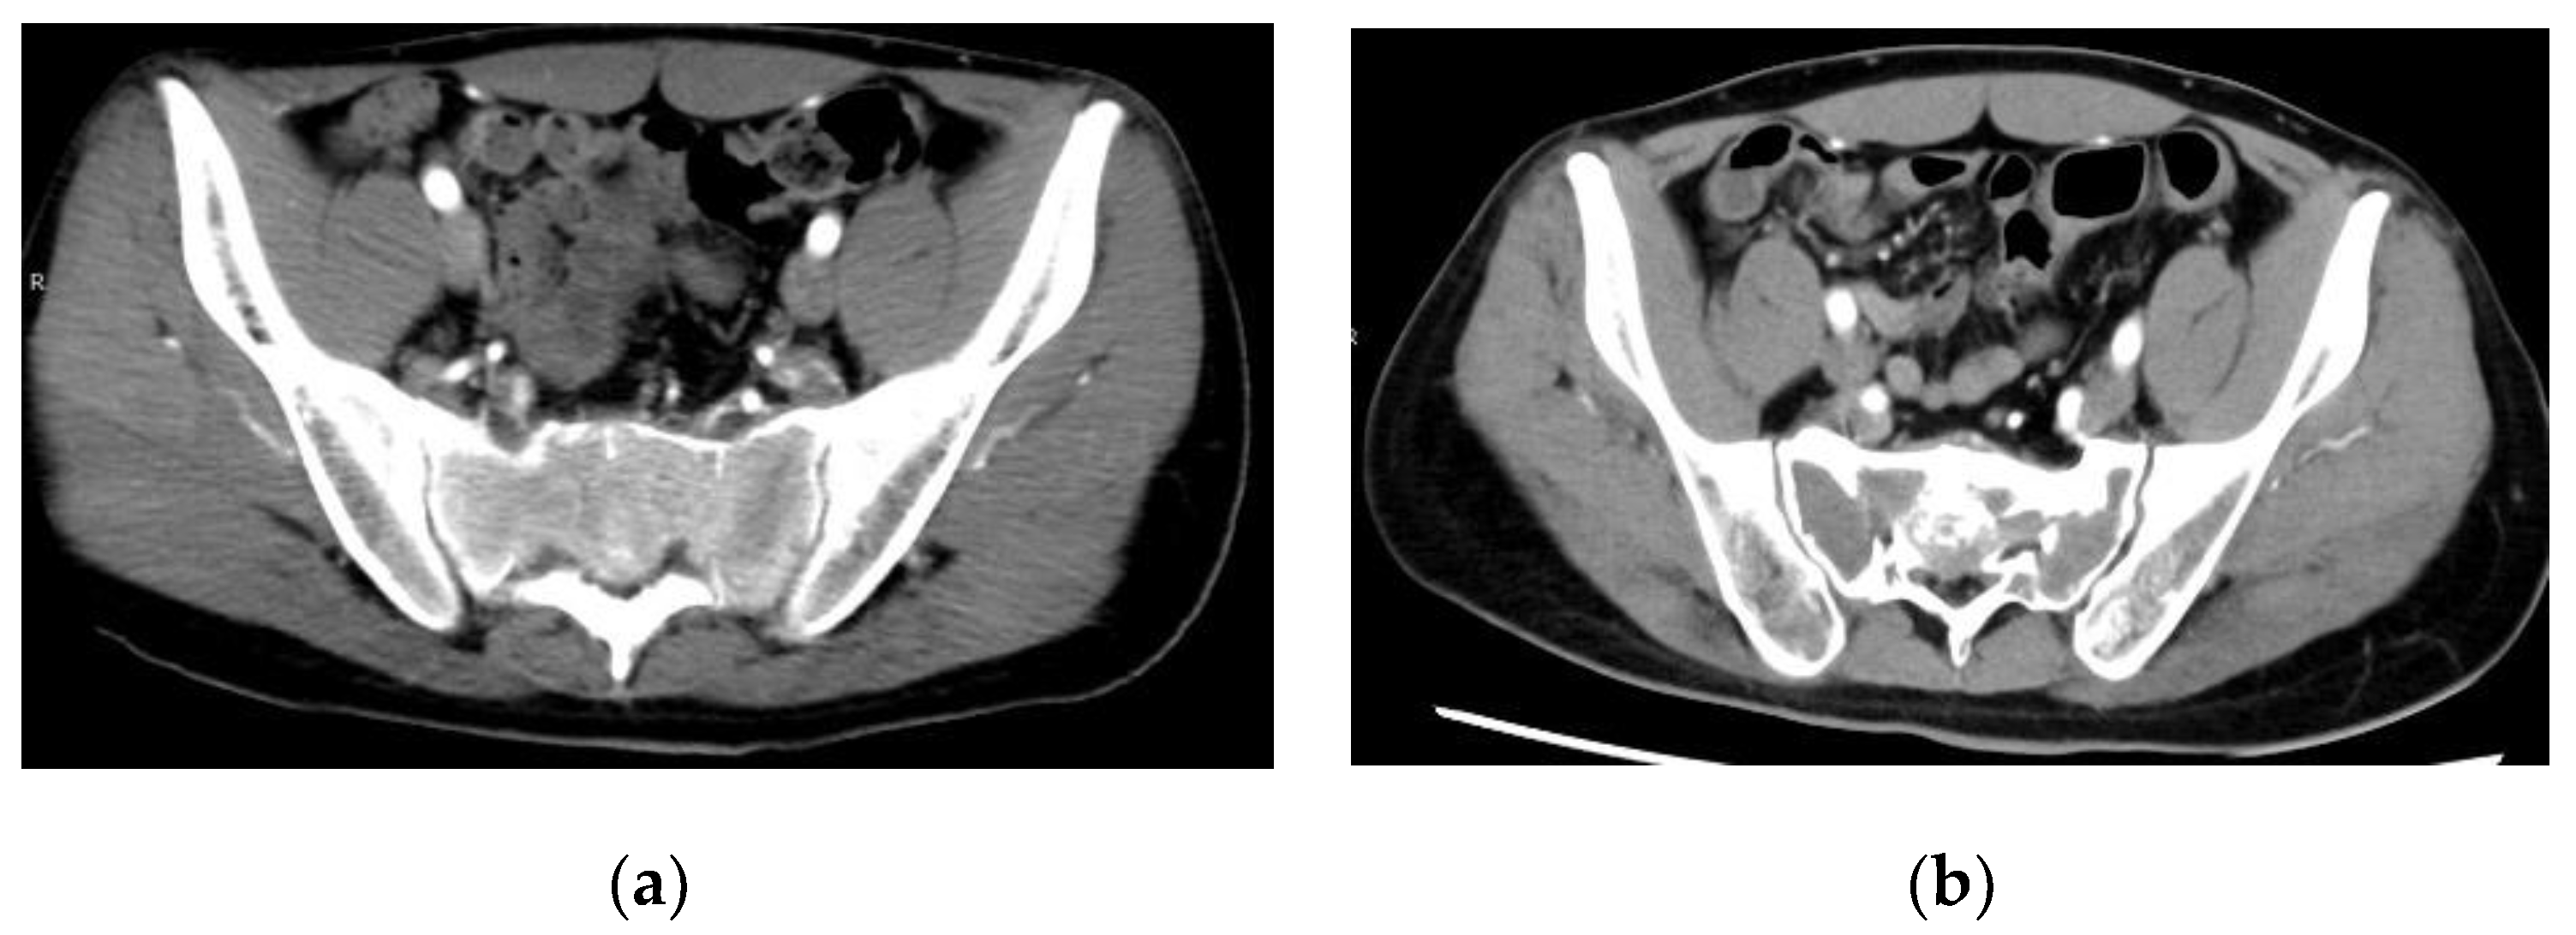

3. Giant Cell Tumor of the Pelvis